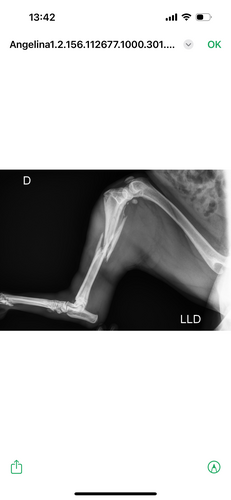

Minha cachorrinha chama Angelina Jolie caiu da laje da minha casa e quebrou a patinha de trás, ela precisa fazer uma cirurgia que custa em torno de 7.000,00. Porém não tenho condições de arcar com o custo sozinha e infelizmente se não fizermos a cirurgia, será necessário amputar a patinha dela 😭. Por favor estou desesperada. Preciso da ajuda de cada um de vocês, pela Angelina Jolie. Desde já agradeço e que Deus lhe dê em dobro.